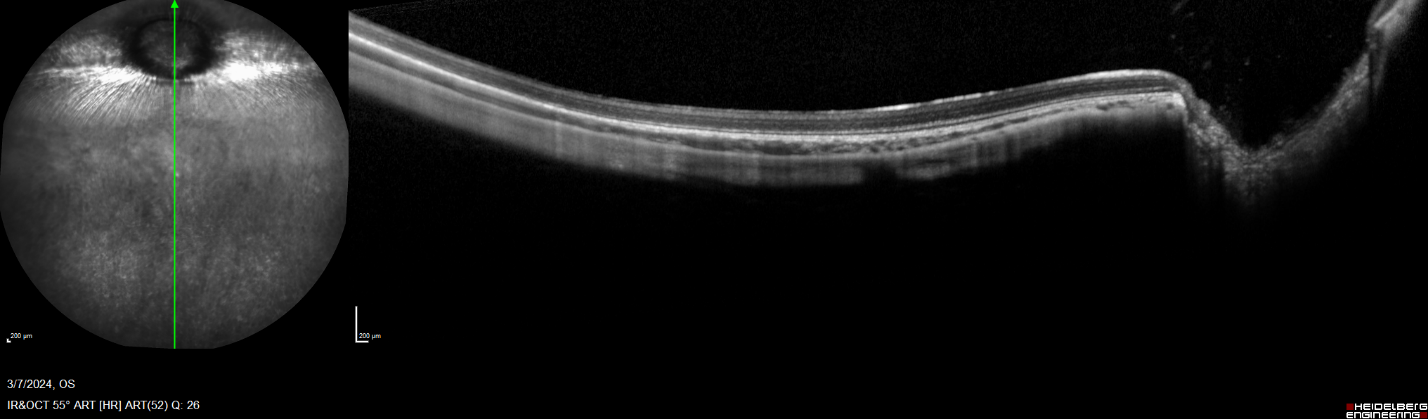

Figure 1. Vertical, single line, wide field OCT scan of a rabbit retina.

• Optical coherence tomography

Uveitis is a group of intraocular inflammatory eye diseases that can result in irreversible blindness and vision loss. The eye is considered immune privileged due to a distinct blood-retinal barrier, however, breakdown of this immune privileged status and blood-retinal barrier can occur, resulting in ocular inflammation known as uveitis.1 At GD3, we induce uveitis through an intravitreal injection of the inflammatory protein TNFα. Following disease induction, our scientific experts conduct a variety of study readouts to shed light on disease pathology and the effect of therapeutic candidates.